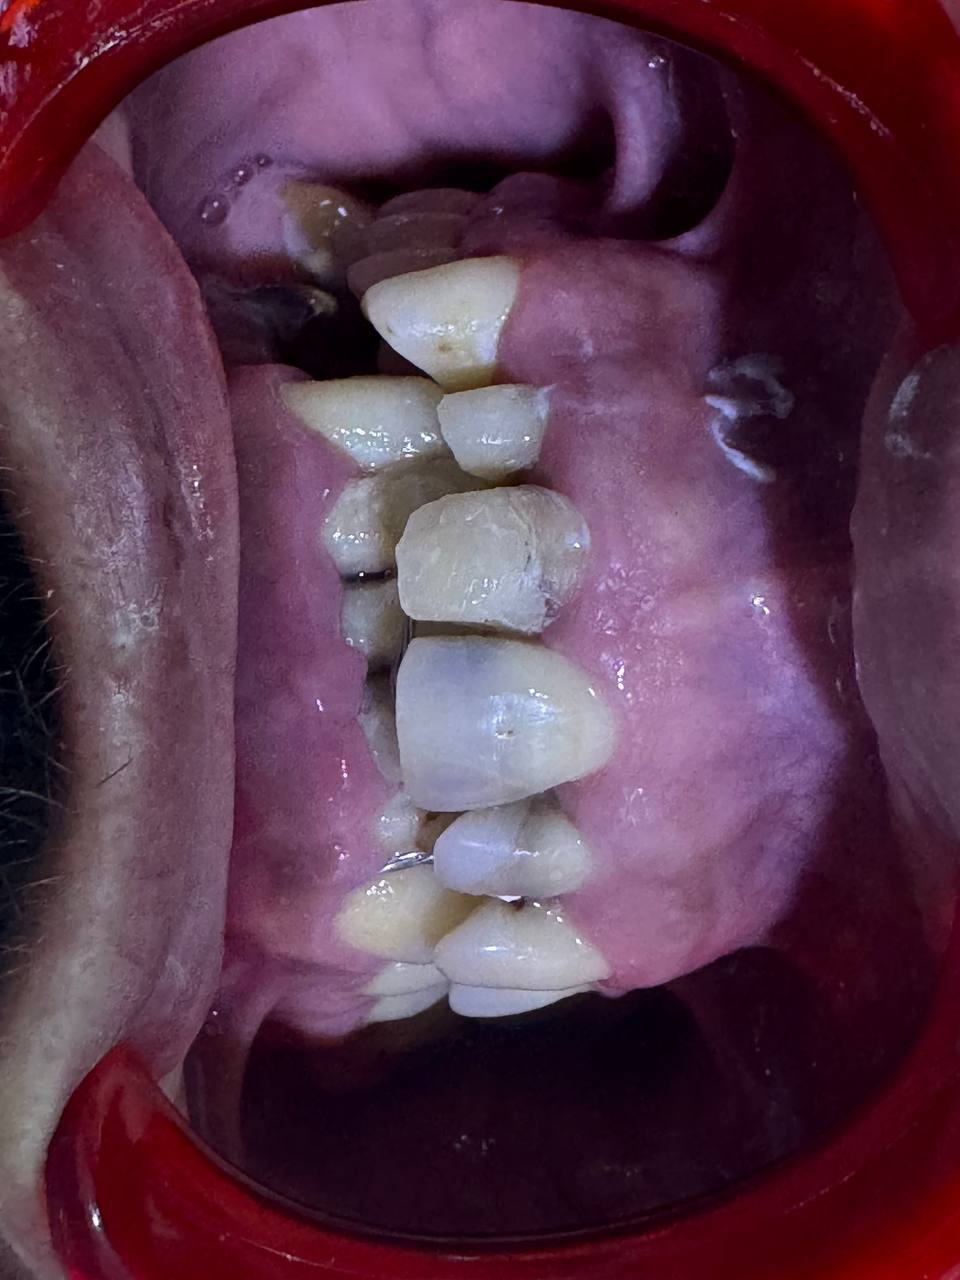

قبل العلاج — أسنان تالفة قبل

جاءنا مراجع وضع الحالة تاعو مفيهاش أمل — وكان عندو الحق. لأن كي يشوف في أسنانه يلقى وضعاً كارثياً ما توقعناش نشوفوه. لكن ما نراه مختلف — وكاين أمل للضحكة هاذي.

🔴

حشوات ضوئية غير متناسقة

حشوات سابقة بألوان وأشكال مختلفة تدمر مظهر الابتسامة

🦷

تسوس داخل الأسنان

تسوس عميق في أغلب الأسنان الأمامية يهدد بقاءها

🎨

كل سن بشكل ولون

لا تناسق بين الأسنان — كل واحدة تبدو مختلفة عن الأخرى

😔

عدم تناسق الابتسامة

المريض يخفي ابتسامته ويتجنب التصوير منذ سنوات

قبل العلاج